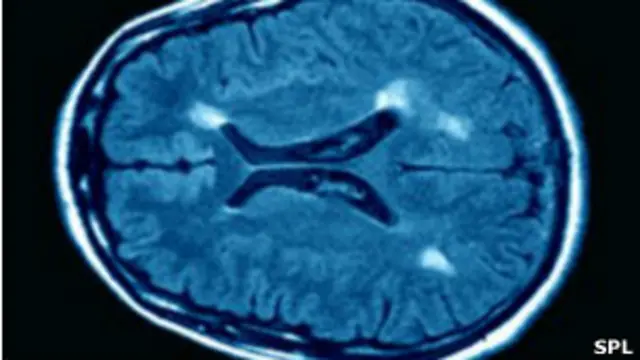

دانشمندان میزان تجمع نوعی پروتئینی را درمغز زنان مبتلا به ام.اس. کشف کردهاند که امیداورند علت شیوع بیشتر این اختلال در میان زنان را توضیح دهد.

در بیماری ام.اس. (مولتیپل اسکلروز) سیستم دفاعی بدن بنا به دلایلی که هنوز کاملا شناخته شده نیست به پروتئینهای موجود در غلاف اعصاب سیستم عصبی مرکزی و پیرامونی (مغز و ستون فقرات) حمله میکند و در نتیجه موجب ایجاد اختلال در حرکت ماهیچهها، عضلات و همچنین اختلال در حفظ تعادل و بینایی میشود.